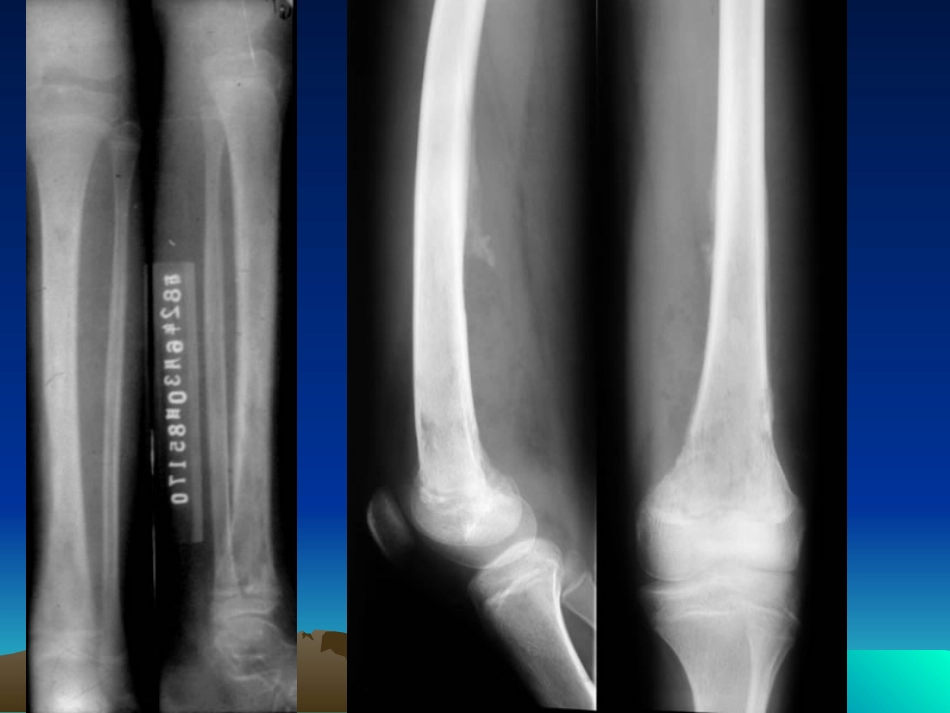

11、急性化脓性骨髓炎、急性化脓性骨髓炎X表现:⑴软组织表现①软组织密度增高、肿胀②肌间隙模糊、消失③皮下组织及肌间界线不清④皮下脂肪内出现水肿成条纹状或网状⑵骨破坏骨质疏松,骨小梁细、中断、消失呈穿凿样⑶骨膜新生与骨质增生葱皮状骨膜反应,骨质破坏与增生并存⑷死骨形成①高密度影②周围有脓腔、骨质破坏,被低密度组织保绕③两端游离④死骨长轴与骨的长轴一直⑸窦道形成⑹病理性骨折肱骨下段急性化脓性骨髓炎。示肱骨下段骨松质内斑点状骨质破坏,骨膜增生呈花边状。急性化脓性骨髓炎。MRI示T2加权横断面低信号的骨皮质外围可见高信号影,是骨膜下脓肿所致。22、慢性化脓性骨髓炎、慢性化脓性骨髓炎X线表现:⑴骨质破坏境界清楚⑵破坏周围有成骨⑶巨大死骨⑷骨皮质增厚⑸骨膜增生⑹骨骼畸形不规则肱骨慢性骨髓炎。示肱骨广泛骨质破坏和增生,骨干变粗。肱骨上段见孤立的大片长方形死骨,其长轴与骨干平行,密度显著增高浓白胫骨慢性骨髓炎。示胫骨骨质增生包壳形成,使骨干明显增粗,包壳内有大片死骨存留。侧位可见通向前方软组织的条状瘘孔。慢性化脓性骨髓炎慢性化脓性骨髓炎二、化脓性关节炎二、化脓性关节炎病理:滑膜感染→→→关节积液→→→脓液中蛋白溶解酶作用→→→关节软骨破坏→→→肉芽组织侵及骨端急性期急性期XX线表现线表现1、关节积液,早期间隙增宽2、关节变窄3、承重大关节中心部位破坏右第二掌骨-食指近节骨化脓性关节炎